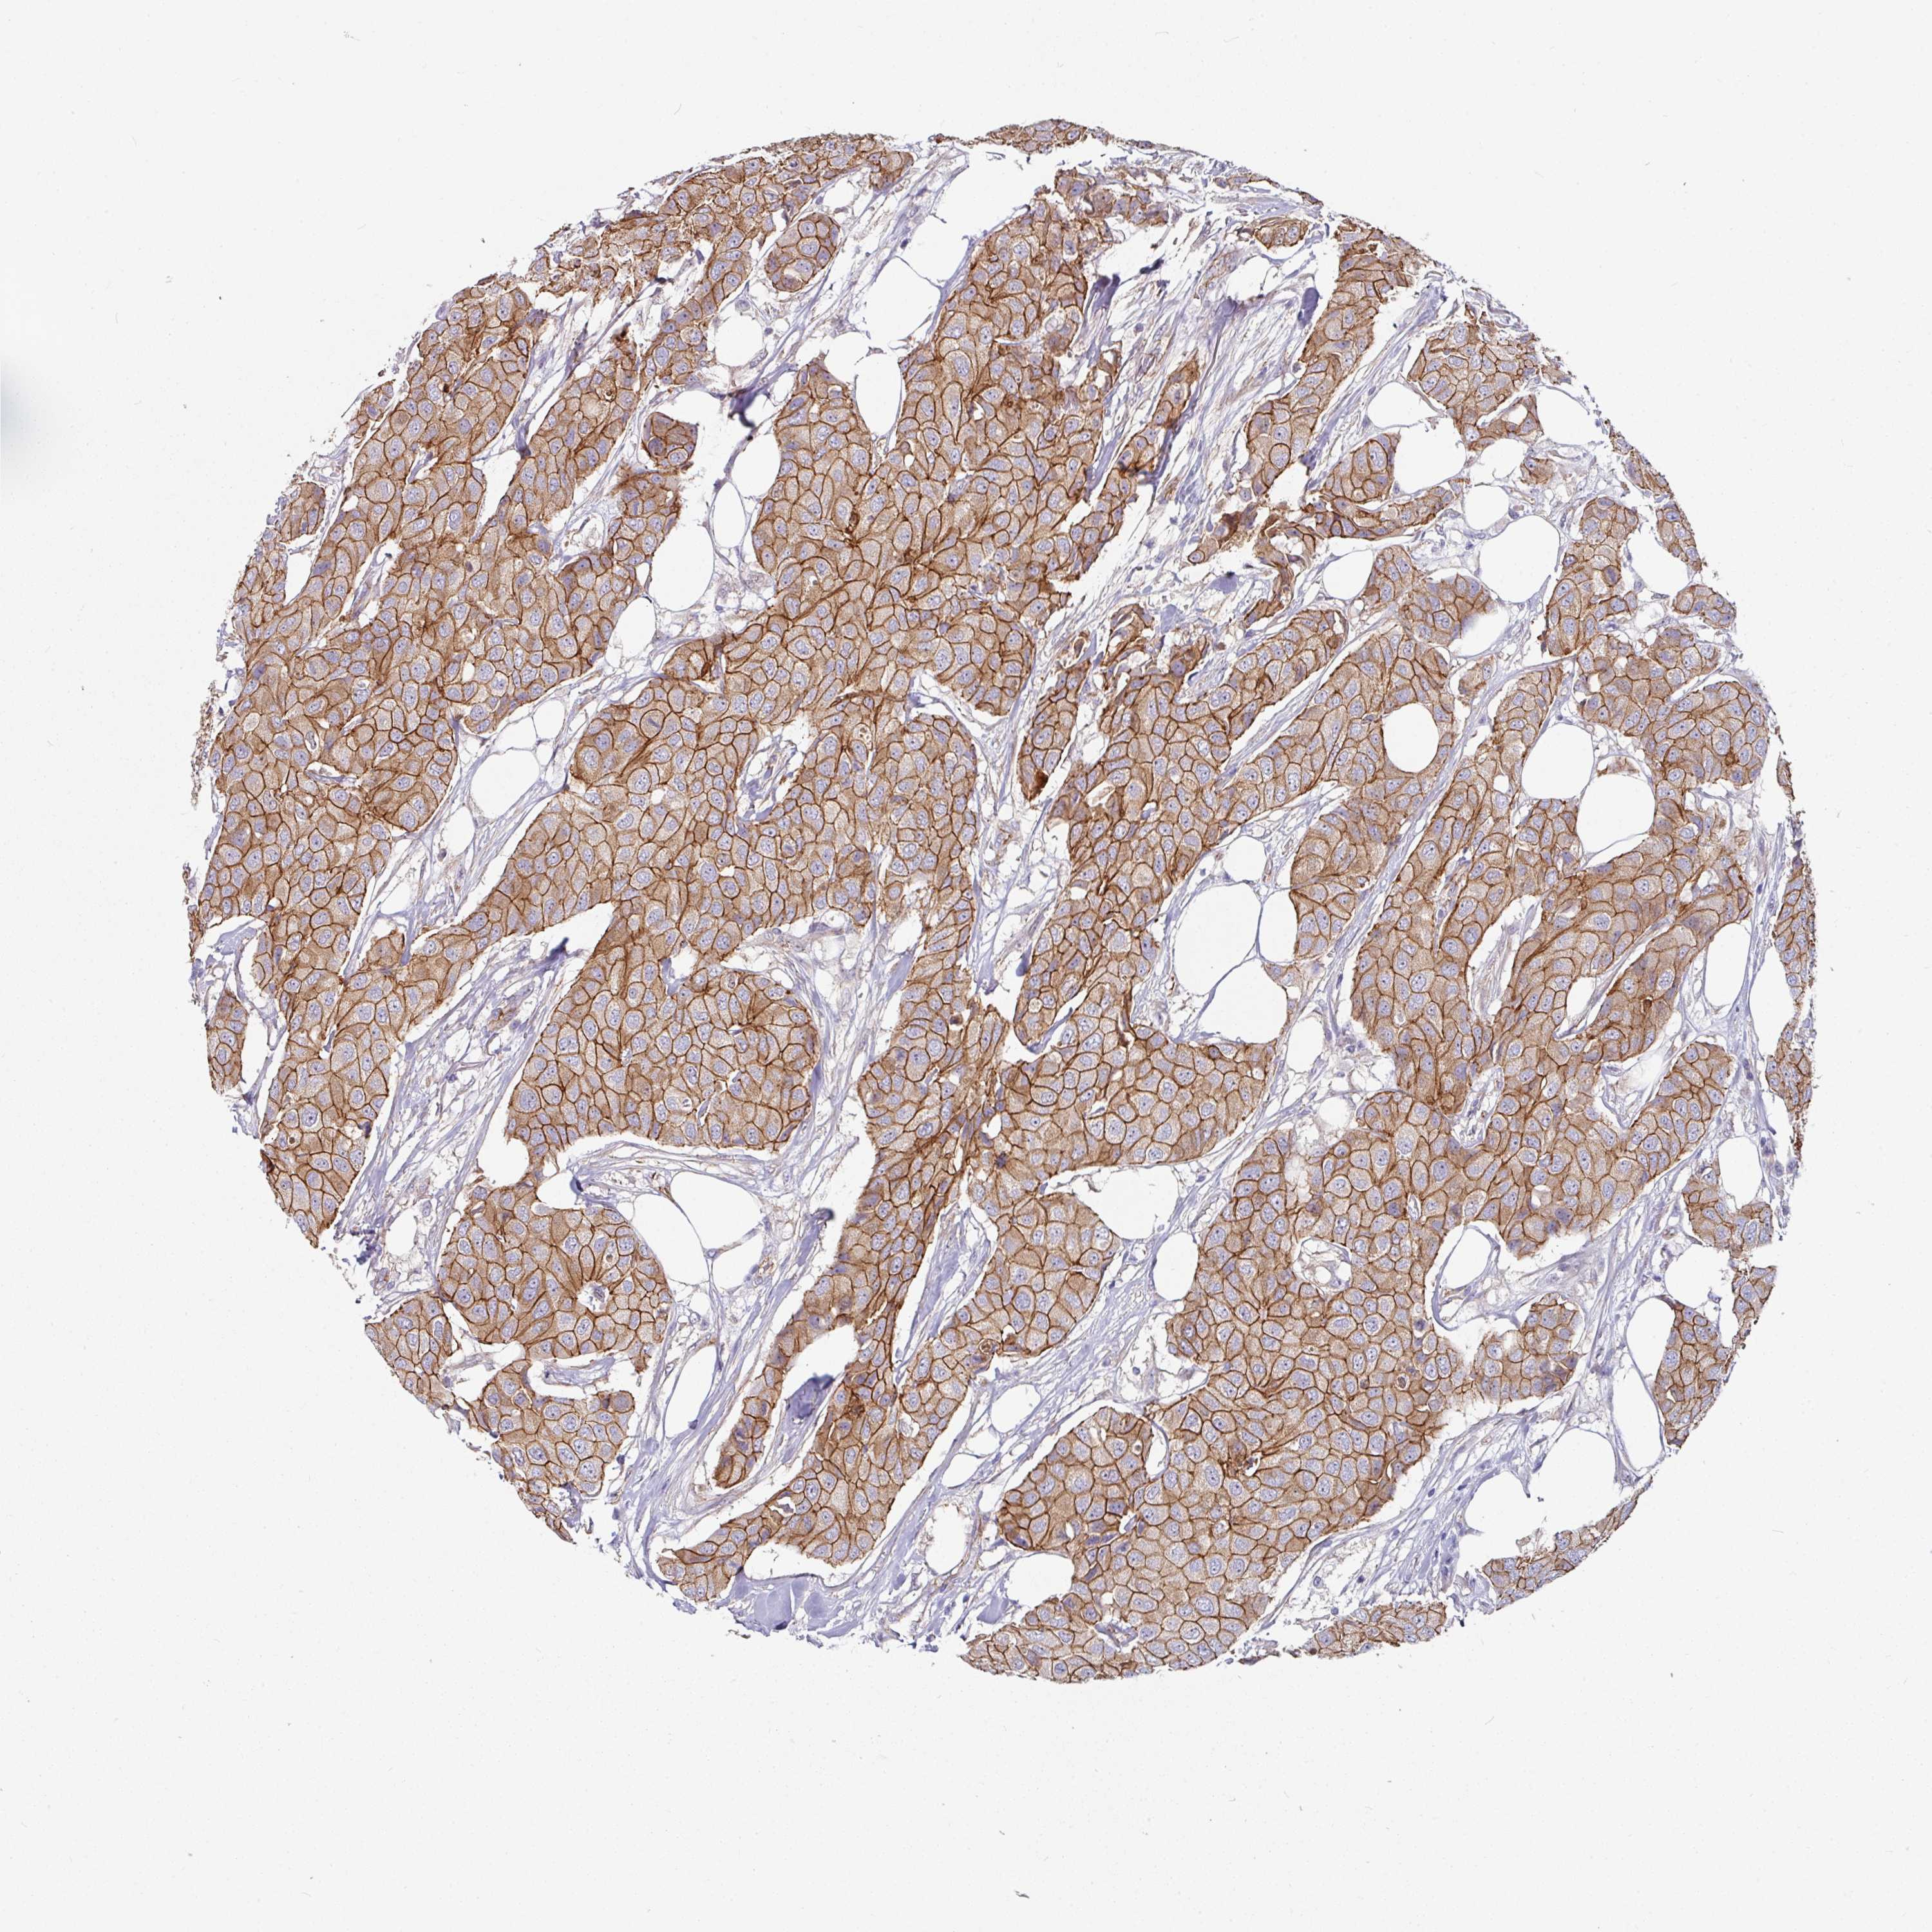

CANCER BREAST CANCER Show tissue menu

BRCA TCGA BRCA VALIDATION PROTEIN EXPRESSION